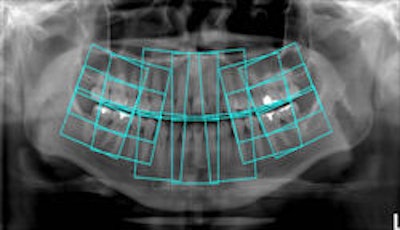

Top, standard panoramic image from a PC-1000 system using a CdTe sensor from Ajat and the PanoACT-1000 tomosynthesis software. Middle, although the anterior teeth are distorted, the posterior teeth no longer have overlapped interproximals. By manually positioning the patient in the system, the contacts are now open. Bottom, the tomosynthesis software then autocorrected the image to bring the front teeth into focus. All images courtesy of Dr. Robert Langlais. |

"In ordinary digital imaging, the software can make the image lighter or darker, change the contrast, magnify, zoom, copy, etc.," he said. "This software goes beyond that. It will autocorrect for positioning errors and generate a new image that is better than the original image. This is a software function that other digital imaging software just can't do."